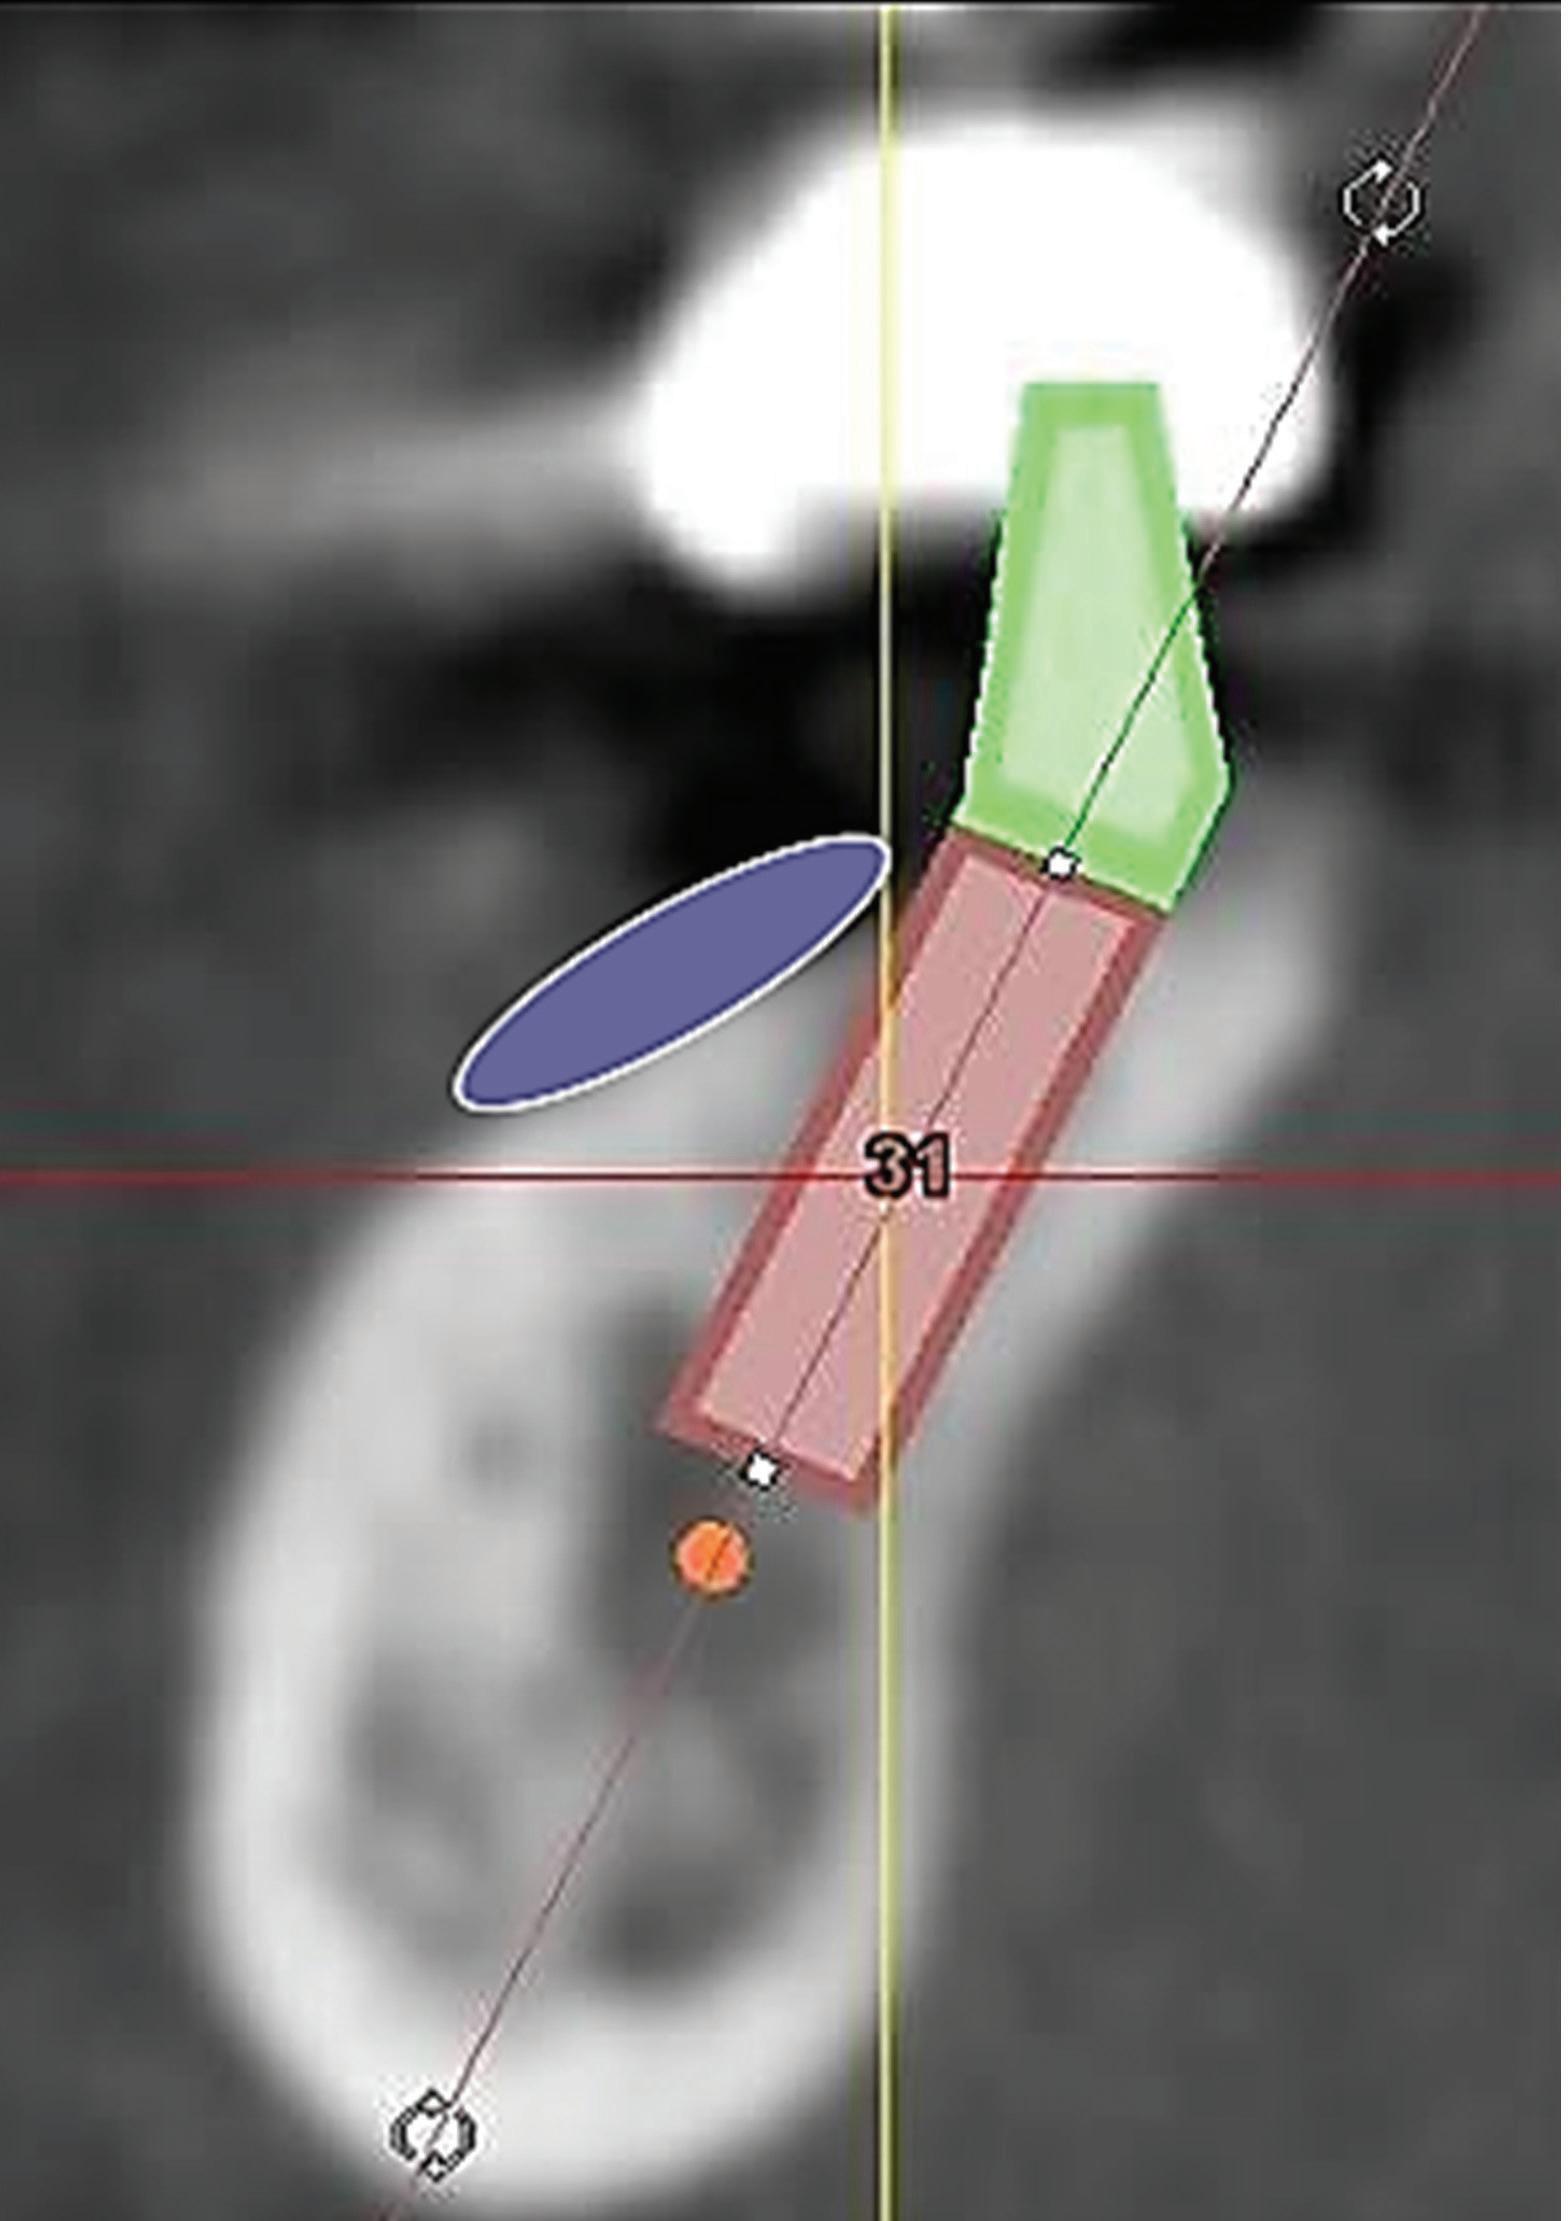

After the CBCT and intraoral scans are completed, it is time to begin the implant planning process using a restoratively driven protocol. This means that the implant-supported restoration is positioned in the ideal alignment in the arch, and the implant is positioned ideally beneath this restoration. The first step of the restoratively driven protocol is a digital wax-up of the missing tooth or teeth. This allows the clinician to determine the correct trajectory of the proposed implant in relation to the tooth and to plan for a screw-retained restoration with the access hole in the middle of the occlusal table. The long axis of the implant also has to be aligned with the proximal contacts because this will be the path of insertion for the prosthesis. If the long axis is parallel to the proximal

contacts, the restoration can be easily seated. When the long axis of the implant is not aligned with the proximal contacts of the adjacent teeth, it may not be possible to use a screw-retained restoration. In select cases, a cement-retained restoration may be necessary. Figure 3 shows implant planning performed using the CBCT images and intraoral scans. The proposed implant is placed in a biologically sound position, and the blue outline of the digital wax-up tooth can be seen. This angled positioning in the esthetic zone would have resulted in an access hole in the facial surface, which is unesthetic. This means that this case will need a cement-retained crown. Using the information from the CBCT and intraoral scans, we know this from the beginning of the case so the restorative portion of the case can be planned accordingly. If the position of the implant had been adjusted enough to place a screw-retained restoration, the result would have been a notable apical perforation, and several millimeters of the implant apex would be outside the bony housing. This would significantly complicate the case and require at least 1 additional grafting surgery, and grafting outside the bony housing is unpredictable. After taking all factors into consideration, it was decided to plan to restore with a cement-retained crown instead of undergoing further surgical procedures.

Fig 1. CBCT images confirm healing of the extraction site after grafting. Fig 2. An occlusal CBCT view reveals the density of the healed graft.

Fig 3. CBCT images of the proposed implant at the site. The digital wax-up can be seen outlined in blue. Placing the implant in a biologically sound position yields a restoration with facial screw access, making a screw-retained restoration an unesthetic option.